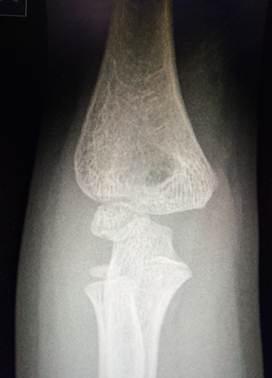

Область локтя в разном возрасте

Василий Оскарович Маркс говорил, что неподготовленный человек на

снимке локтевого сустава здорового ребенка найдёт восемь переломов. Очень даже

может быть – рентгенологическая картина локтя ребенка в возрасте от года до

четырнадцати лет насыщена ядрами окостенения и зонами роста, которые легко

принять за костный отломок или осколок, особенно если в анамнезе есть травма.

7 лет – 10 лет

В этом возрасте начинается процесс окостенения медиального вала

блока, в котором появляются мелкие, неправильной формы ядра окостенения. В 8

лет появляется ядро окостенения вершины локтевого отростка. Чуть позже к нему

добавляются мелкие ядра - спутники. К концу периода появляется ядро окостенения

латерального надмыщелка.

Возраст 7 лет. Ядро окостенения головчатого возвышения плавно

распространяется в латеральный вал блока и он начинает прослеживаться. Рядом с

ним заметно маленькое линейное ядро окостенения в медиальном вале блока. Появилось два маленьких ядра окостенения

вершины локтевого отростка.